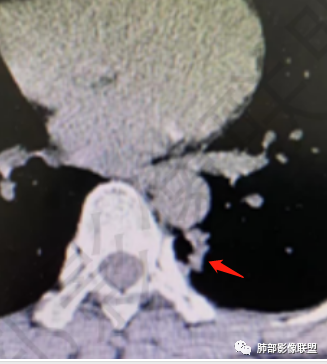

看纵隔窗:实性成分密度不高,囊张力高,内有间隔,偏胸膜侧,实性部分内部支气管聚集。

实性区域边缘平直、凹陷

首先囊的位置?为啥没考虑是空洞?空洞张力偏低一些,一般在中央一些,所以不太支持,纵隔侧几乎无壁,不太支持空洞。

囊实性?这部位,第一印象要警惕--隔离症

隔离症——需要增强确定,看起来附近似有体动脉正常,没增强底气不足。

真菌?不太符合,因为囊腔。如果不考虑隔离症?就要警惕腺癌系列,总体看来不是很支持。